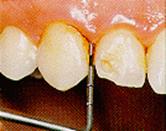

Código

4: bolsa patológica de 5,5 mm. o más, el área negra de la sonda

no se ve.

Nota:

si el diente examinado se halla con un valor 5,5 mm. o más, este

valor se le asigna al sextante.